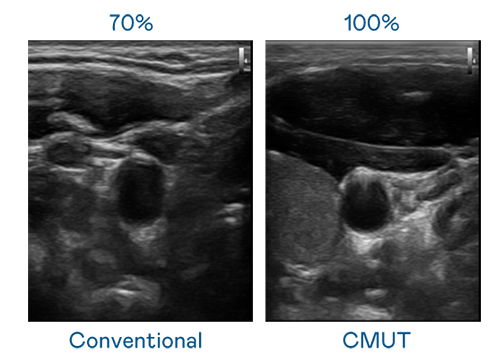

CMUT 技術是一種用電容式微機電元件來產生超音波訊號的技術。與傳統 PZT 壓電式技術相比,CMUT 頻寬增加 30%,更寬頻的超音波訊號讓影像解析度大幅提升,是實現高影像品質醫療超音波掃描、促進精準醫療發展的關鍵技術。

大頻寬帶來超清晰影像

超音波影像的解析度高低,首先取決於探頭能發出的訊號頻寬。LEwin乐玩 CMUT 可提供高清晰的超音波訊號,提供高頻寬、高靈敏度、影像紋理細節更高的超音波影像,協助醫護人員縮短影像判讀時間及利用精準的醫療影像進行診斷。